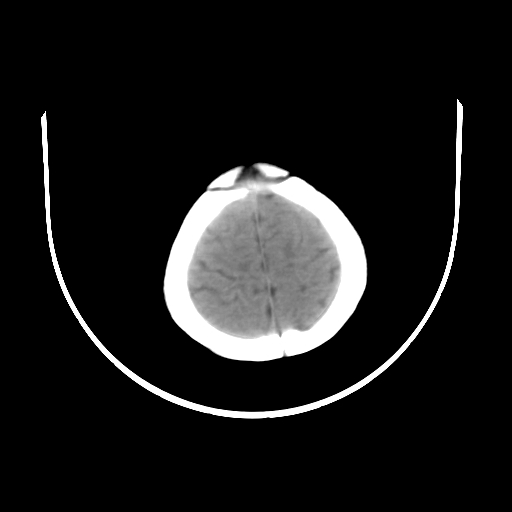

女,10个月,头外伤三天,伤后爱哭闹,吃奶少,睡觉不踏实。

左侧颞极蛛网膜囊肿

1)左侧颞极蛛网膜囊肿。2)第四脑室出血?

1、左侧颞极蛛网膜囊肿;2、第四脑室出血?3、右侧顶叶脑裂畸形伴灰质异位?